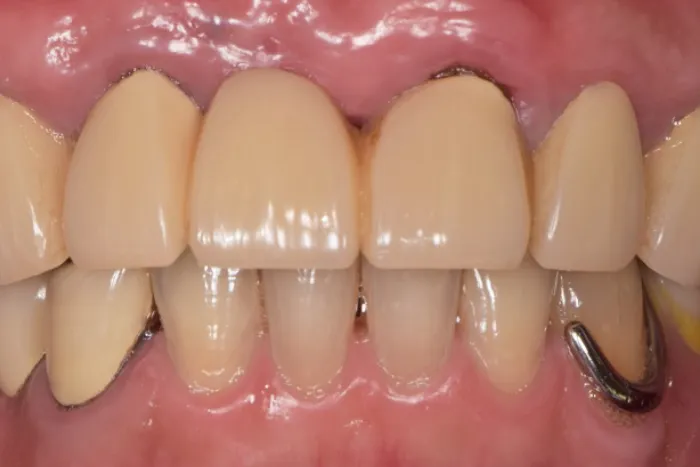

症例② 前歯が一本だけ長いのが気になる

Before

After

| 主訴 | 前歯が一本だけ長いのが気になる |

|---|---|

| 治療期間 | 8ヶ月 |

| 治療費 | 結合組織移植術 77,000円 ※保健治療の金額は含みません |

| 治療内容 | 根管治療・結合組織移植術・レジン前装冠 |

| 治療のリスク | 術後の腫脹・出血 / 歯肉退縮による金属色の露出 |

▲治療のコメント

歯を抜いて歯茎が退縮してしまったことが原因で歯が長くなっていました。なので、上顎口蓋から結合組織を移植することで退縮した歯肉を再建しました。その上でブリッジのやり直しを行いました。